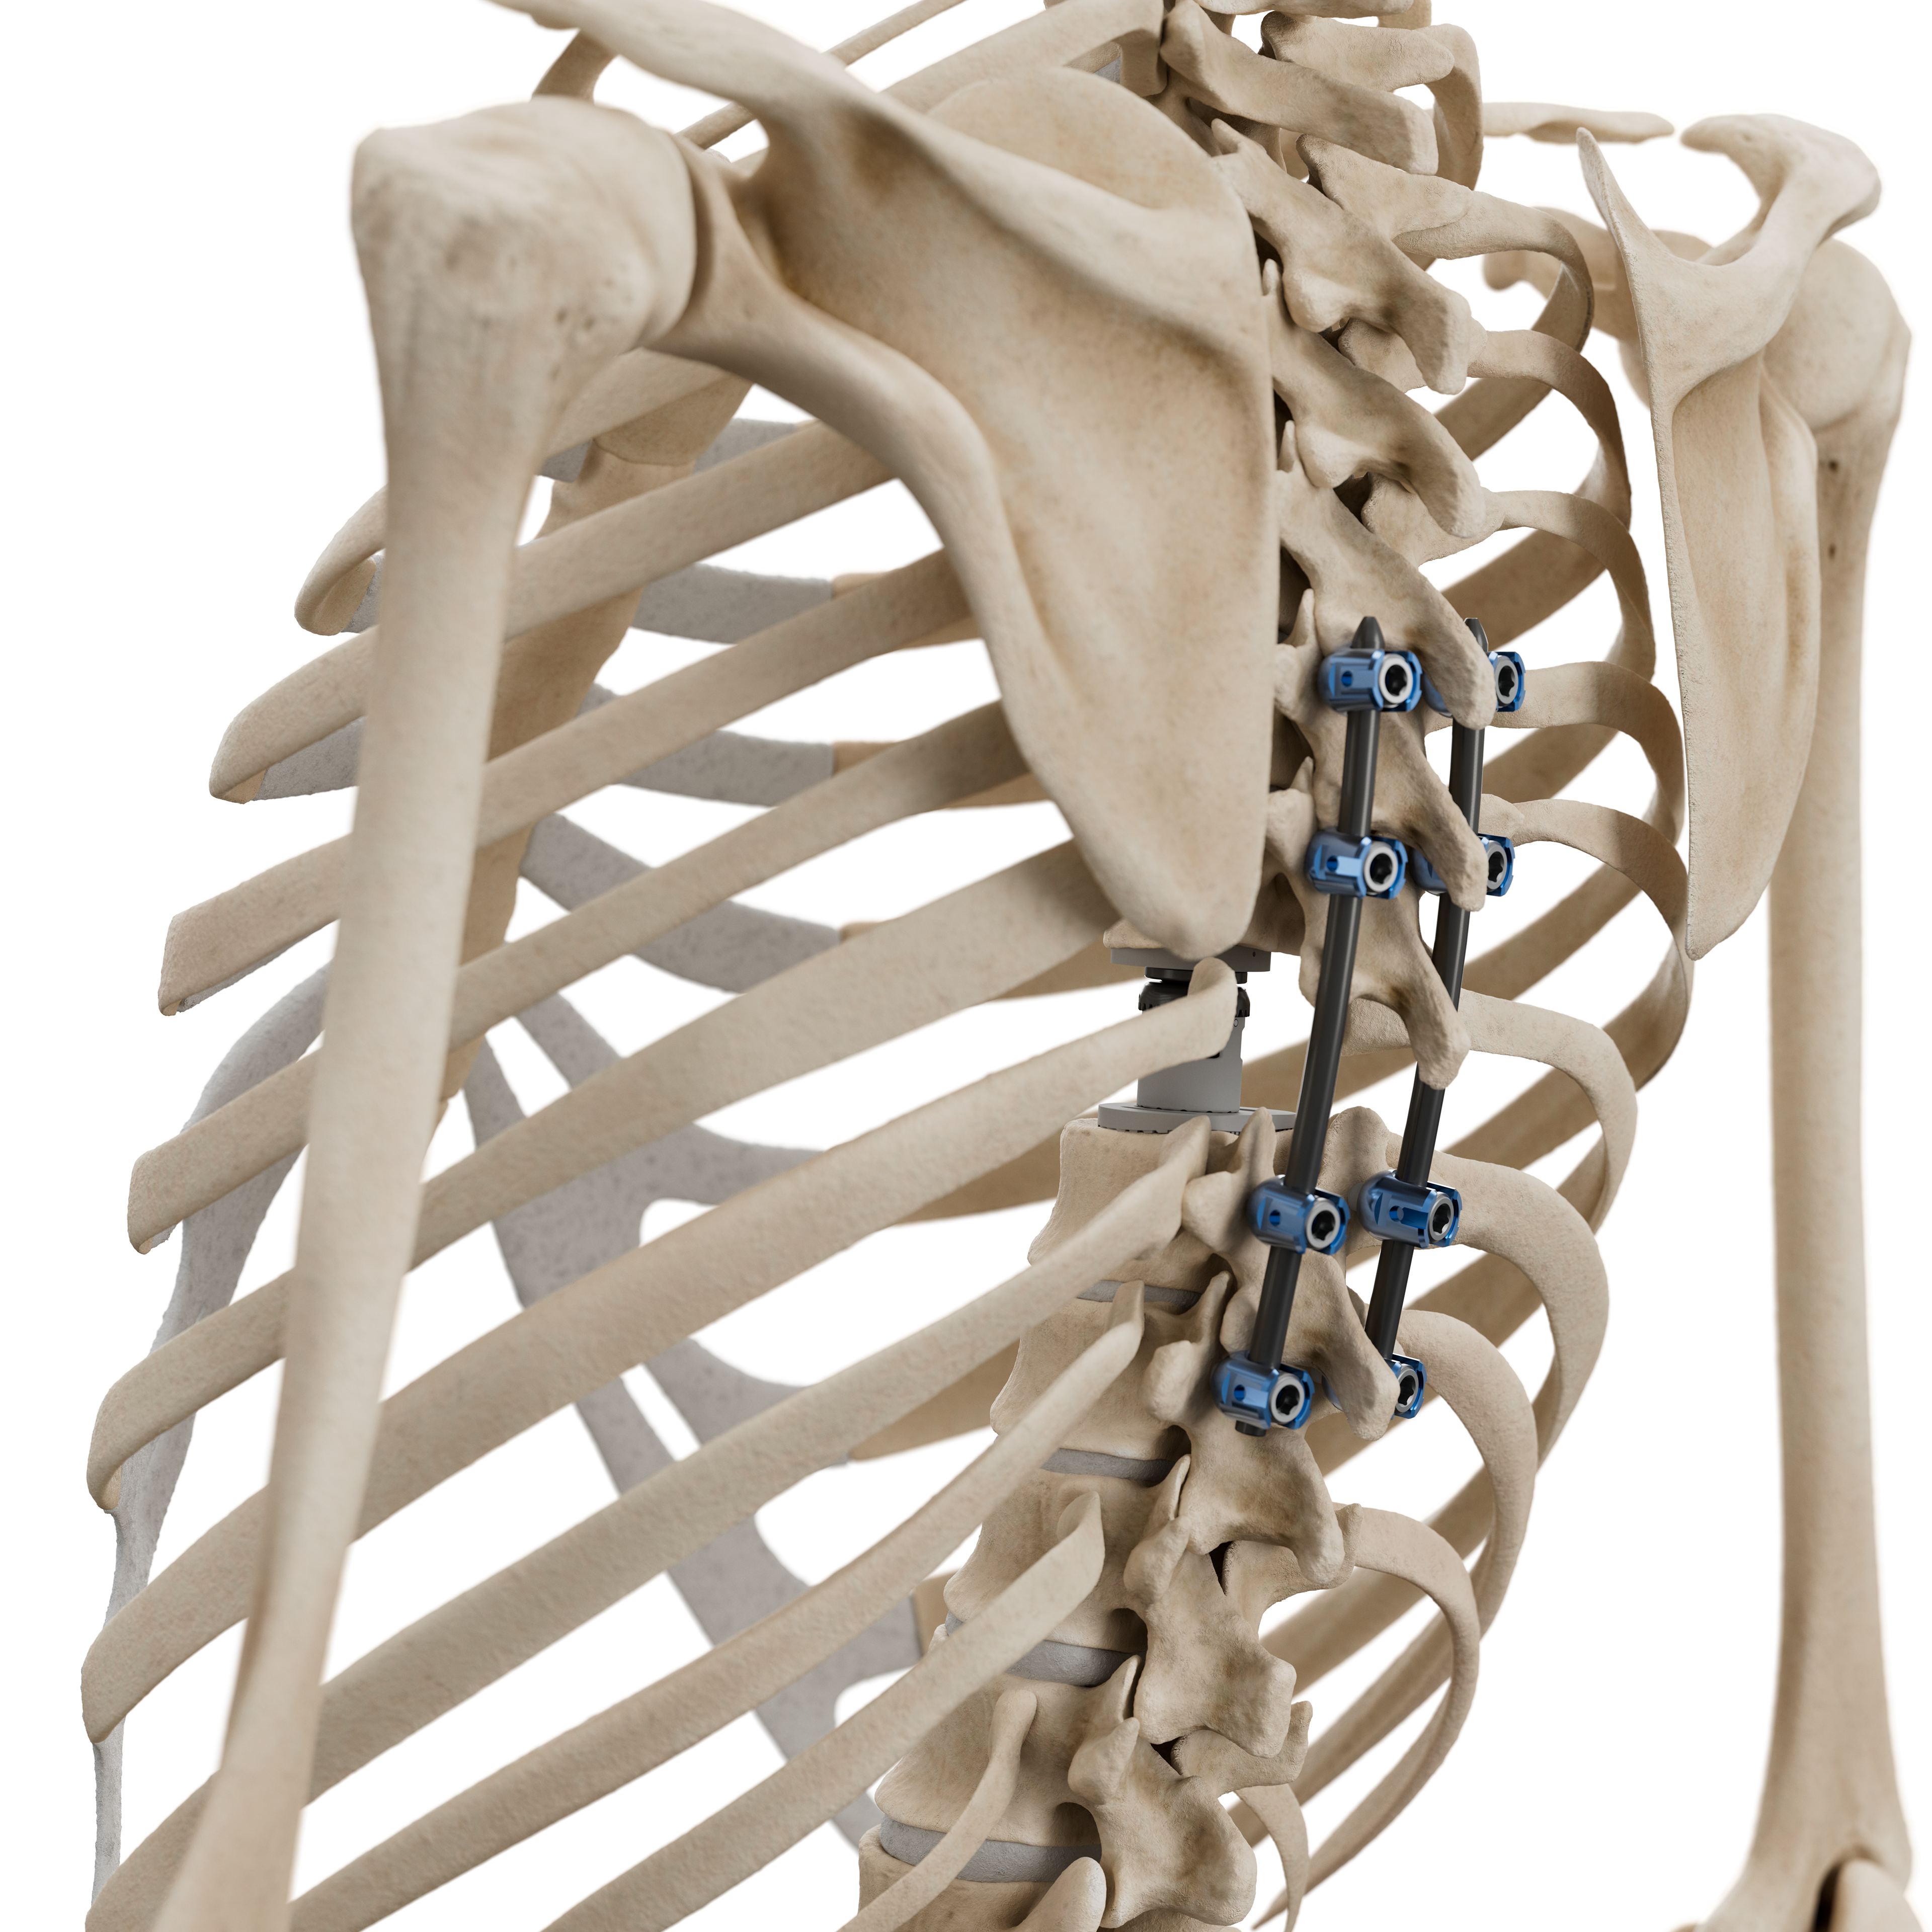

Die Produkte von ICOTEC Medical, die "Black Armor" verwenden, finden Anwendung in der Wirbelsäulen- und Orthopädiechirurgie. Zum Beispiel werden Bandscheibenimplantate aus "Black Armor" hergestellt, um degenerative Erkrankungen der Bandscheibe zu behandeln und die Stabilität der Wirbelsäule wiederherzustellen.

Ein grosser Vorteil von "Black Armor" ist seine Durchlässigkeit für Röntgenstrahlen, was die Nachbehandlung und Bildgebung im vergleich zu herkömmlichen metlllischen Implantaten stark vereinfacht. Um dies zu veranschaulichen, sind folgende Bilder entstanden.